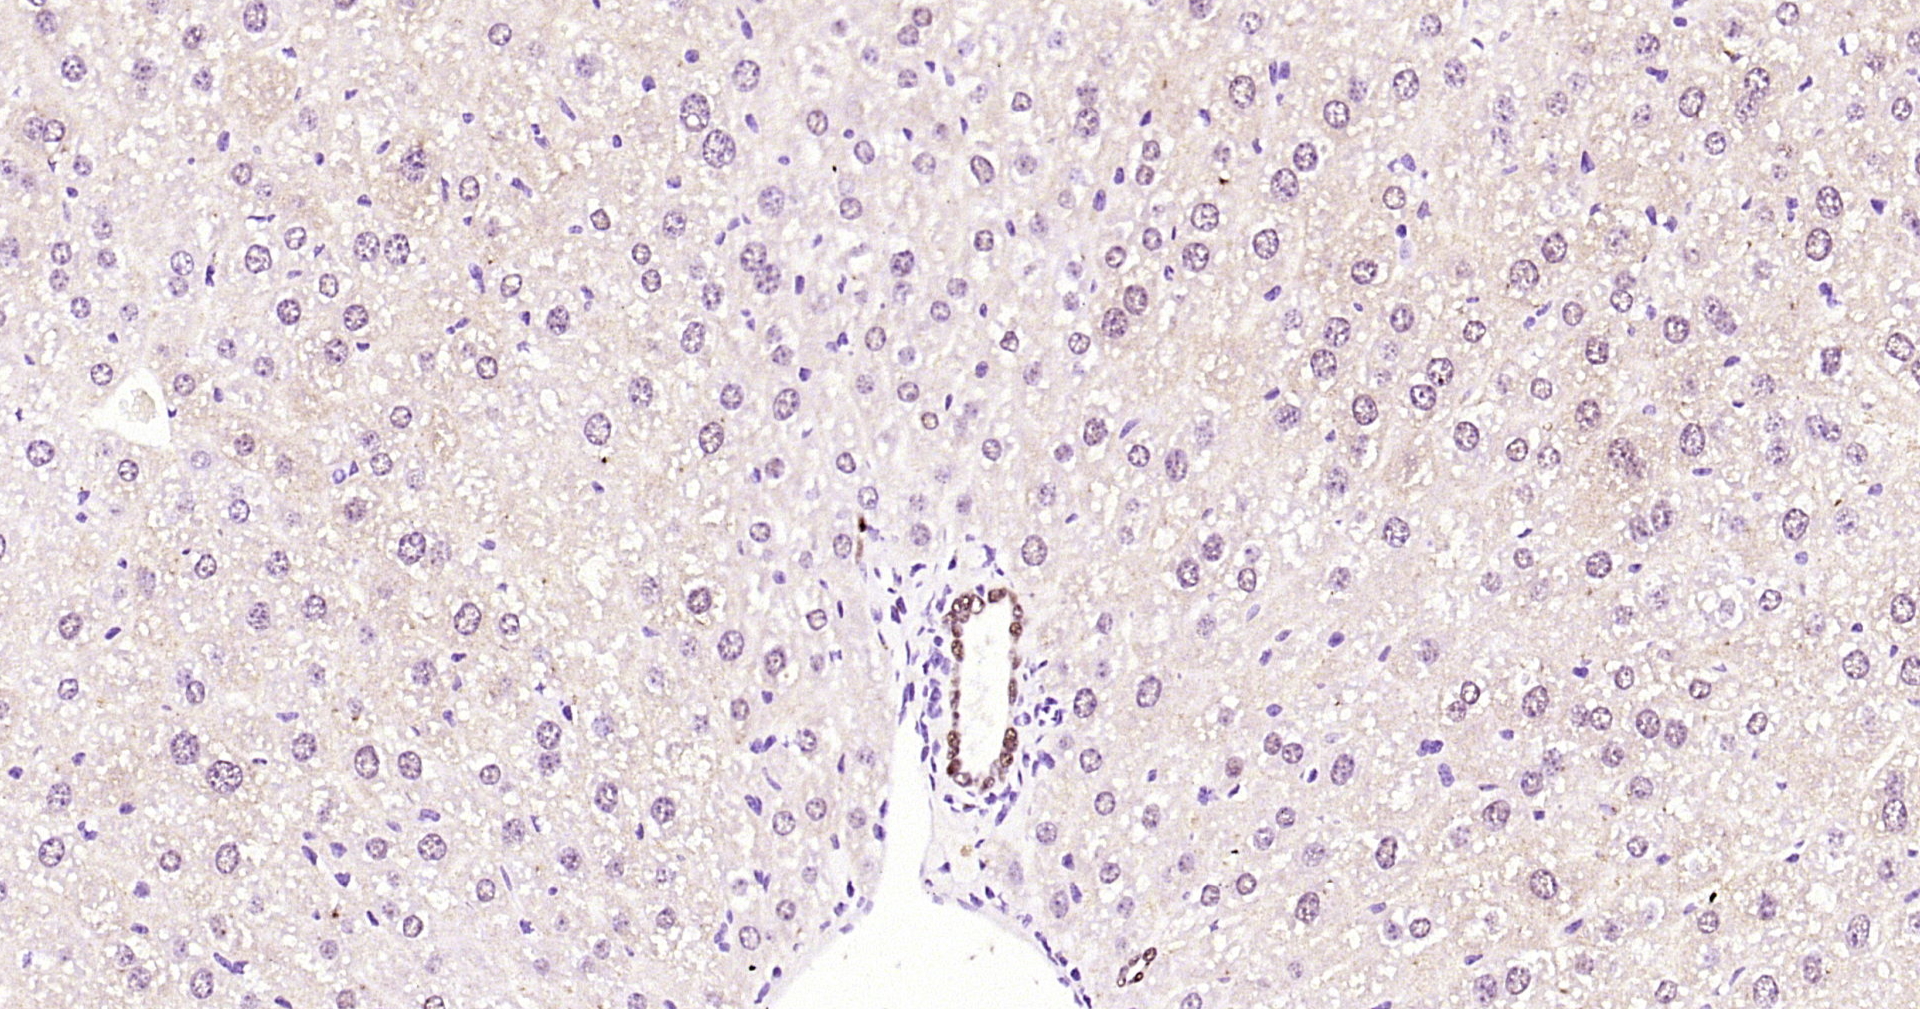

• IHC-P

IHC-P IHC-P1:200-1000